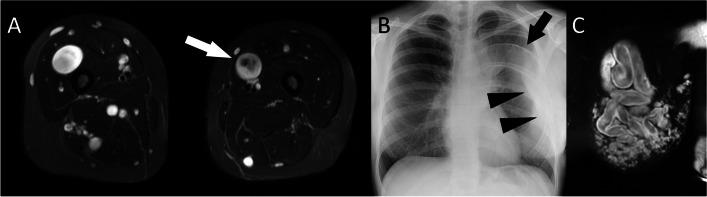

Somatic overgrowth disorders comprise a wide range of rare conditions that present with focal enlargement of one or more tissue types. The PI3K-AKT-mTOR pathway is a signalling pathway that induces angiogenesis and cell proliferation, and is one of the most commonly overactivated signalling pathways in cancer. The PI3K-AKT-mTOR pathway can be up-regulated by genetic variants that code for proteins in this pathway, or down-regulated by proteins that inhibit the pathway. Mosaic genetic variations can result in cells that proliferate excessively in specific anatomical locations. The PIK3CA-related overgrowth spectrum (PROS) disorders include CLOVES syndrome, macrodystrophia lipomatosa, and Klippel-Trenaunay syndrome among many. The neurofibromatosis type 1 (NF1) gene encodes neurofibromin which down-regulates the PI3K-AKT-mTOR pathway. Thousands of pathological variants in the NF1 gene have been described which can result in lower-than-normal levels of neurofibromin and therefore up-regulation of the PI3K-AKT-mTOR pathway promoting cellular overgrowth. Somatic overgrowth is a rare presentation in NF1 with a wide range of clinical and radiological presentations. Hypertrophy of all ectodermal and mesodermal elements has been described in NF1 including bone, muscle, fat, nerve, lymphatics, arteries and veins, and skin. The shared signalling pathway for cellular overgrowth means that these radiological appearances can overlap with other conditions in the PIK3CA-related overgrowth spectrum. The aim of this review is to describe the genetic basis for the radiological features of NF1 and in particular compare the appearances of the somatic overgrowth disorders in NF1 with other conditions in the PIK3CA-related overgrowth spectrum.